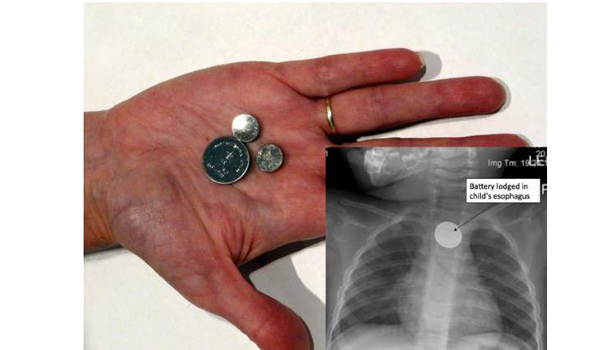

4. Baterai Seukuran Kancing

Gadget yang paling banyak menyebabkan kematian

Baterai seukuran kancing sering digunakan pada jam tangan atau pada remote control. Mainan anak-anak dan berbagai benda lain yang memerlukan baterai berukuran kecil.

Namun siapa sangka jika benda ini masuk dalam daftar gadget yang paling banyak menyebabkan kematian.

National Capital Poison Center (NCPC) di Washington, DC mencatat. Bahwa sejak 1985 telah lebih dari 60.000 orang yang menelan baterai seukuran kancing tersebut.

Lebih dari 3.500 orang mengalami cidera, dan 9 diantaranya bahkan mengalami kematian. Kasus tersebut rata-rata terjadi pada anak-anak yang usianya masih berada di bawah enam tahun.

Saat baterai tersebut tertelan oleh anak-anak, maka dapat terjebak pada tenggorokan. Akibatnya anak-anak tersebut bisa mengalami luka bakar kimia yang parah.

Efeknya bisa dalam beberapa menit pasca baterai tersebut tertelan, setelah dua jam dapat membakar lubang kerongkongan dimana baterai tersebut telah tersangkut.

Menyikapi hal ini, maka orang tua harus ekstra hati-hati. Setidaknya jangan sampai meletakan baterai berukuran kecil pada daerah yang mudah dijangkau oleh anak-anak.